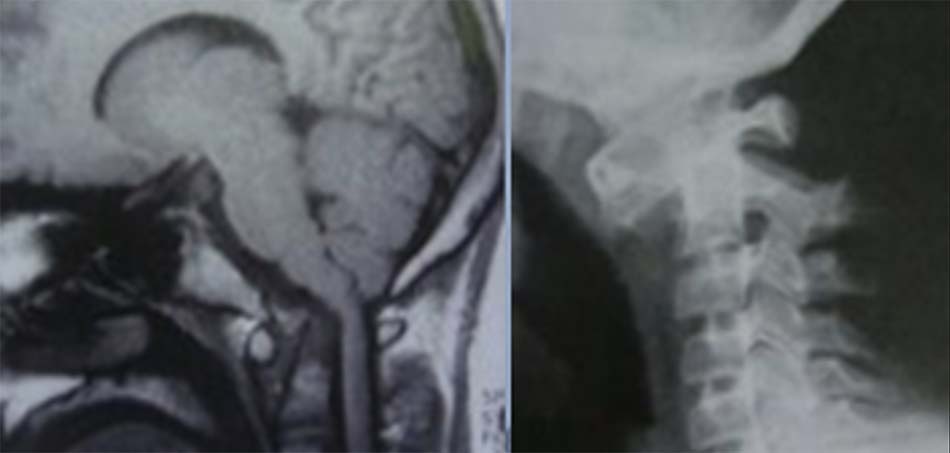

2.4.1. Tật lồng đáy sọ

Tật lồng đáy sọ là bất thường vùng cổ chẩm có nguy cơ gây tử vong cao do mất vững đội – trục và có thể gây trật đội – trục khi chỉ gặp chấn thương nhỏ. Điều trị phẫu thuật gặp nhiều khó khăn. Nhiều quan điểm cho rằng chèn ép thân não phía trước nên được giải ép bằng đường mổ lối trước qua khoang miệng và sau đó nẹp cổ chẩm. Trong dị dạng Chiari, có thể phẫu thuật giải ép mai chẩm và cố định cổ chẩm [4]. Phương pháp khác đã được áp dụng khi phẫu thuật can thiệp làm giãn khớp đội – trục và vít khối bên [2]. Một nghiên cứu tiến hành trên 190 bệnh nhân tật lồng đáy sọ do Goel và cộng sự tiến hành nhằm đánh giá sự thích hợp trong phương pháp phẫu thuật. Dựa vào sự kết hợp với dị dạng Chiari, tật lồng đáy sọ được chia vào 2 nhóm bao gồm không có sự kết hợp với dị dạng Chiari hoặc có Chiari. Với những bệnh nhân tật lồng đáy sọ không có Chiari kèm theo thích hợp hơn khi được phẫu thuật giải ép đường miệng và nếu có Chiari kèm theo thì phải giải ép lỗ chẩm. Sau phẫu thuật giải ép lối trước ở những bệnh nhân không có Chiari nên được cố định cổ chẩm tuy nhiên tỷ lệ cố định cổ chẩm ở nhóm giải ép lỗ chẩm trong Chiari hạn chế hơn [3].

Chẩn đoán Tật lồng đáy sọ được xác định trên chẩn đoán hình ảnh [1], có 3 đường cơ bản được xác định trên phim chụp nghiêng và đường trên phim chụp thẳng như sau:

- Đường Chamberlain: nối từ bờ dưới lỗ chẩm tới bờ dưới khẩu cái cứng. Triệu chứng lâm sàng xuất hiện khi đỉnh mỏm nha nằm phía trên đường kẻ này. Tuy nhiên điều bất lợi khi xác định đường Chamberlain do bờ dưới lỗ chẩm khó xác định trên phim nghiêng.

- Đường McGregor: nối từ điểm thấp nhất của vòng cung chẩm tới bờ trên thành sau khẩu cái cứng, nếu đỉnh mỏm nha nằm trên đường này 4,5 mm, có sự bất thường.

- Đường Mc Rae: bản chất là đường kính lỗ chẩm, đường nối từ bờ trước đến bờ sau lỗ chẩm. Không có triệu chứng lâm sàng nếu đỉnh mỏm nha nằm dưới đường này.

![Tật lồng đáy sọ trên cắt lớp vi tính và cộng hưởng từ [1]](https://chanthuongvacotsong.bachmai.gov.vn/wp-content/uploads/2021/01/tat_long_day_so.jpg)

Đường Fischgold and Metzger: xác định trên phim thẳng trước sau là đường thẳng nối 2 điểm giữa chân mỏm chũm và nền sọ, bình thường đường này nằm phía trên đỉnh mỏm nha 10,7 mm và trên khớp đội chẩm 11,6 mm. Nếu khoảng cách này ngắn lại chẩn đoán xác định dị dạng lồng đáy sọ.